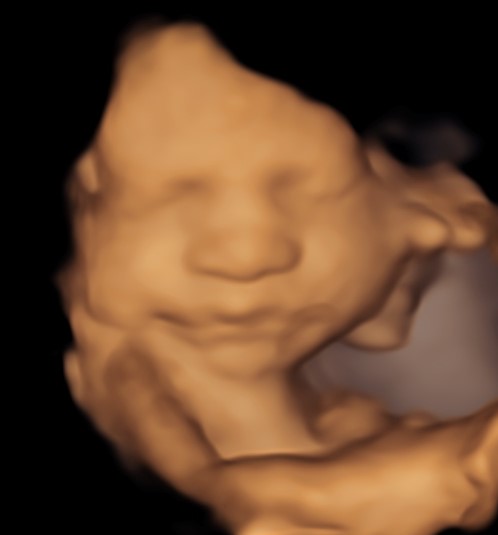

Monmouth County’s First 4D/5D/HD Live Ultrasound Studio

4D/5D/HD Ultrasound Gallery

Gallery